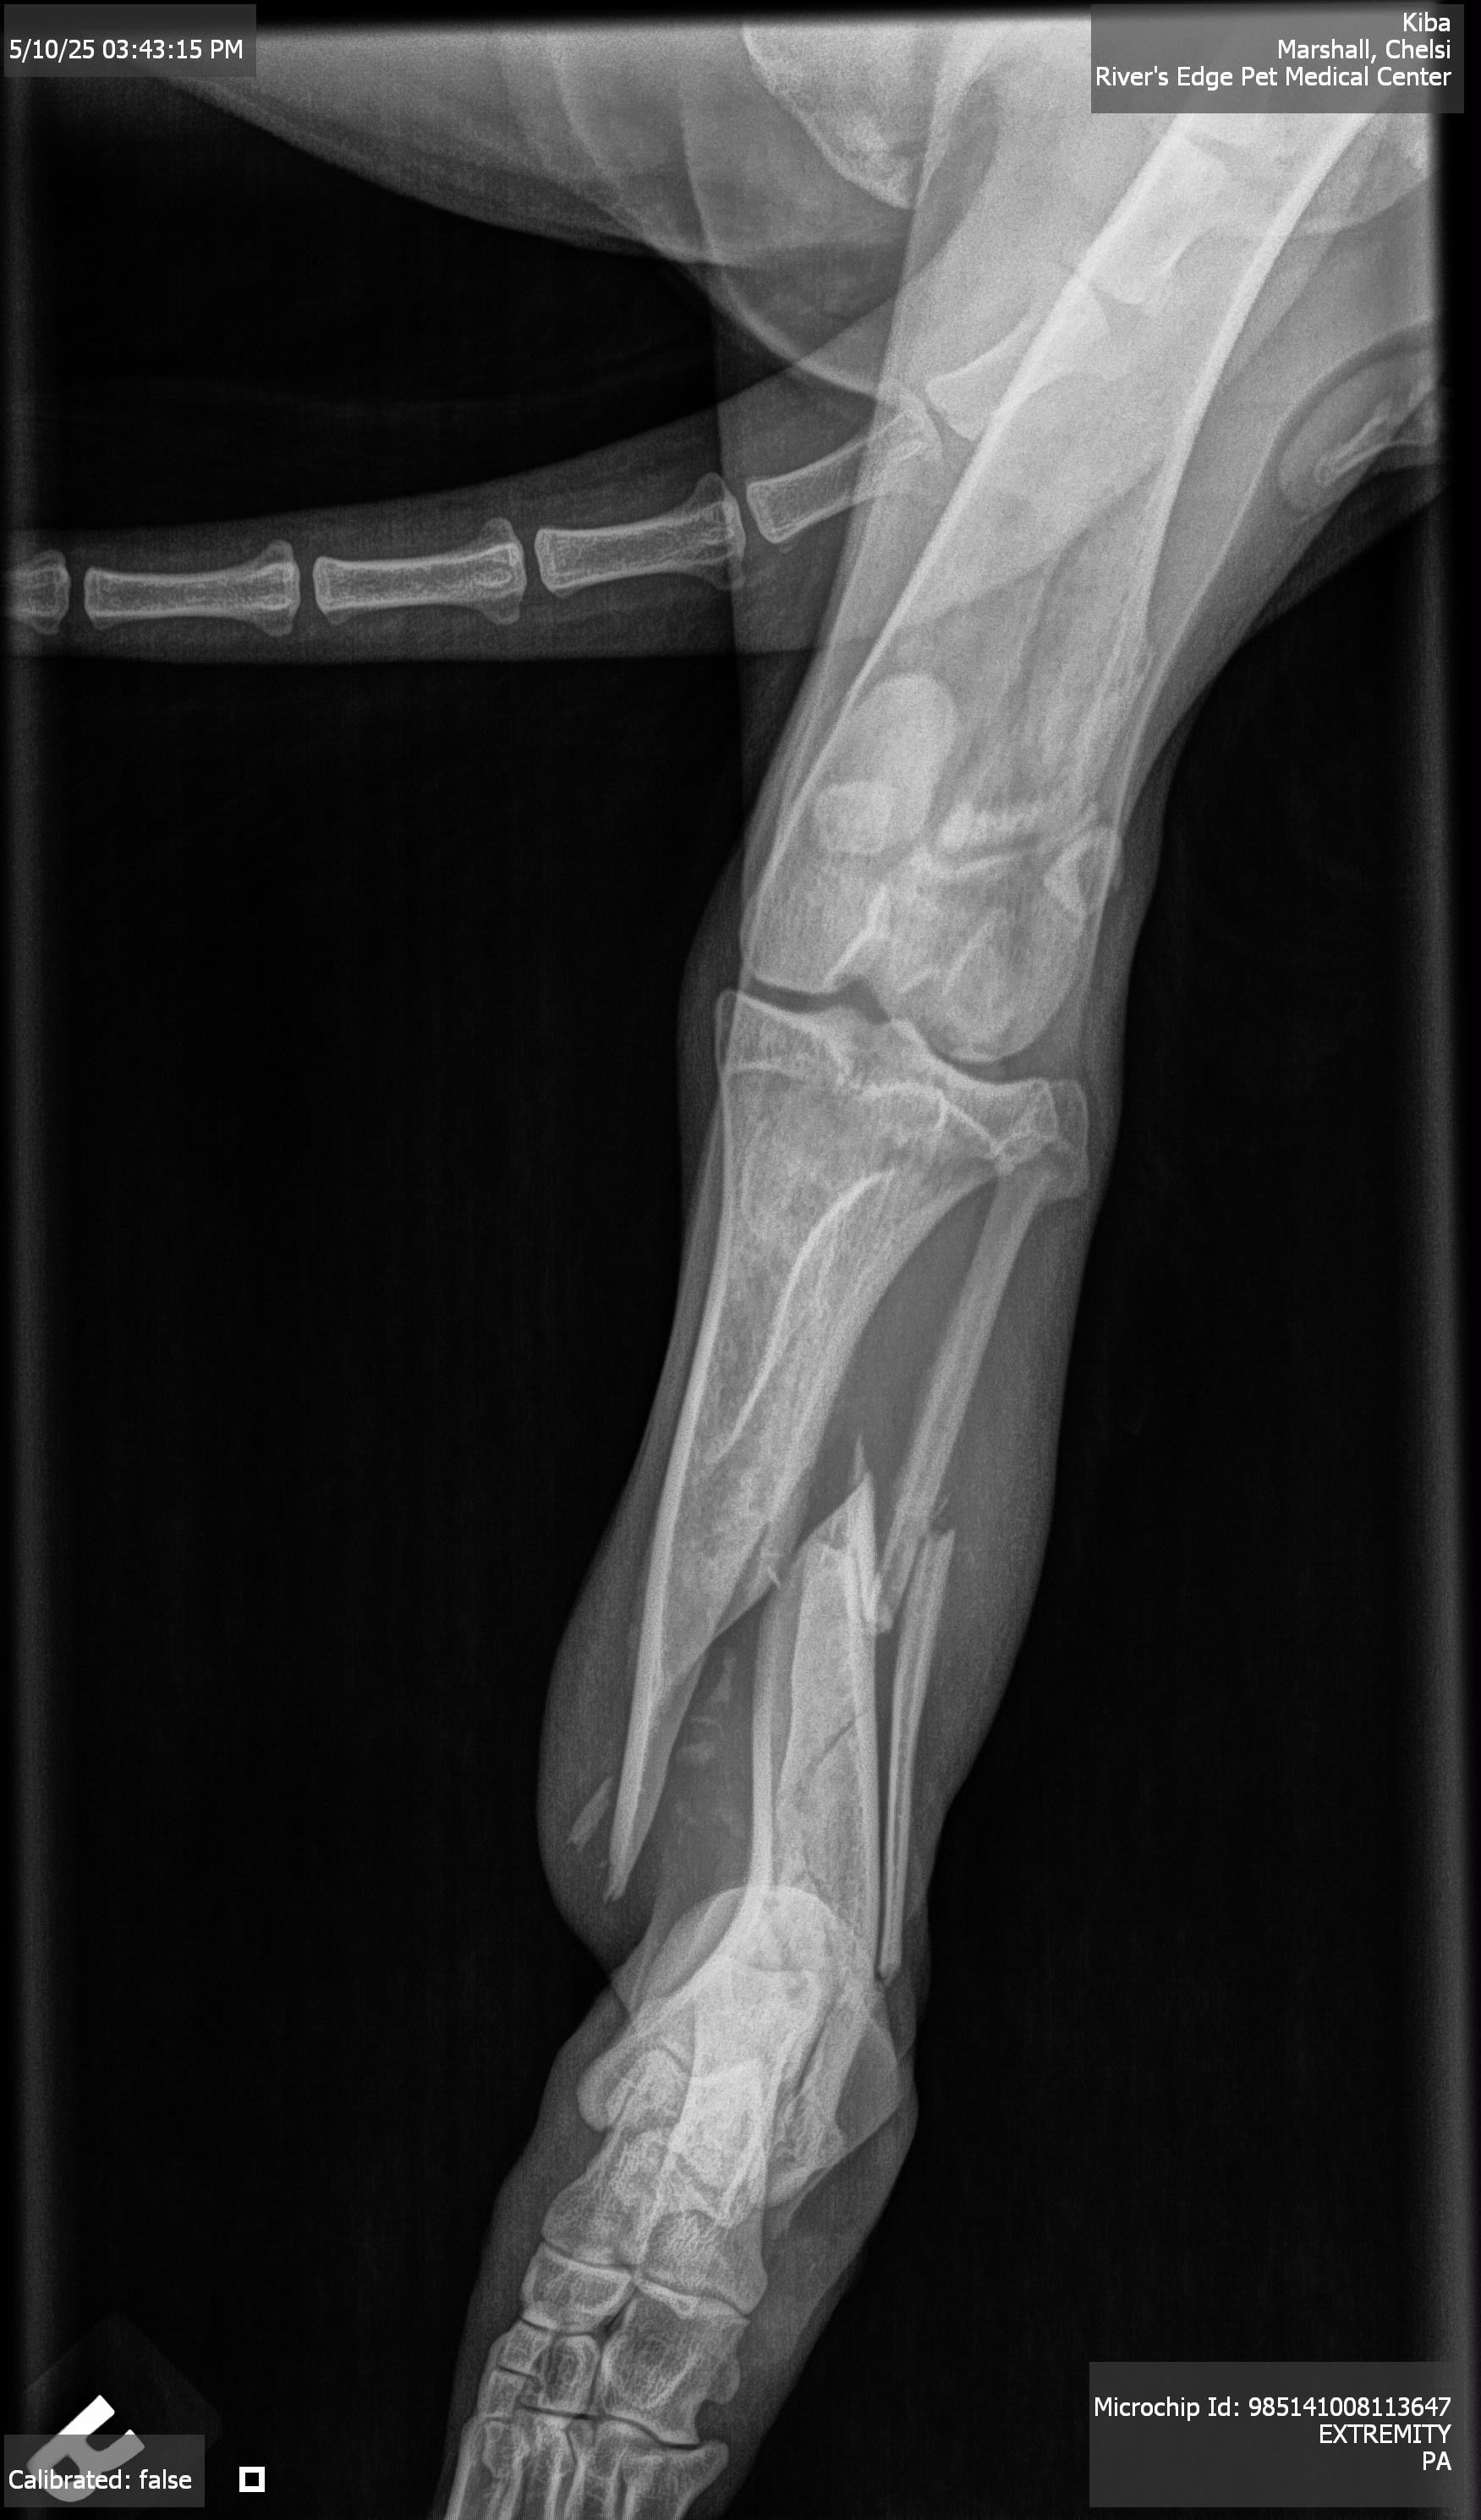

Update: Kiba had his appointment with the OSU veterinary hospital who will be doing the surgery and his leg is worse then we thought. His tibia is mangled and has calluses forming in the bone. The vet believes he was hit by a car the first day he went missing so there has been time for the bones to try and “heal”. So they are going to have to do a lot of work to try and fix his leg. I have added a photo of the itemized cost for the surgery. Please if anyone would like to help us get our boy back to health please donate. I appreciate every one of you more than words could ever express. If anyone would like to donate directly to OSU this is the number to call [phone redacted] and say it’s for Kiba and the owner is Chelsi Holmes.

Hi everyone, my name is Chelsi and a lot of you saw our story about our dog Kiba who was missing for almost 2 weeks. While our boy was gone, he got hurt and has multi bone spiral fracture to his tibia and fibula and is going to need surgery to fix his leg. This is going to be an expensive surgery and we could use any help that we can get to help Kiba get back to his happy, healthy self. I understand that these are trying times for everyone, but anything helps. His consultation for surgery is with OSU vet on Wednesday and I will post all of their findings and itemized list of what they are going to do for him and cost when I have it. I have added the pictures of his x rays that our vet took and pictures of his wounded leg before and after going into the vet.